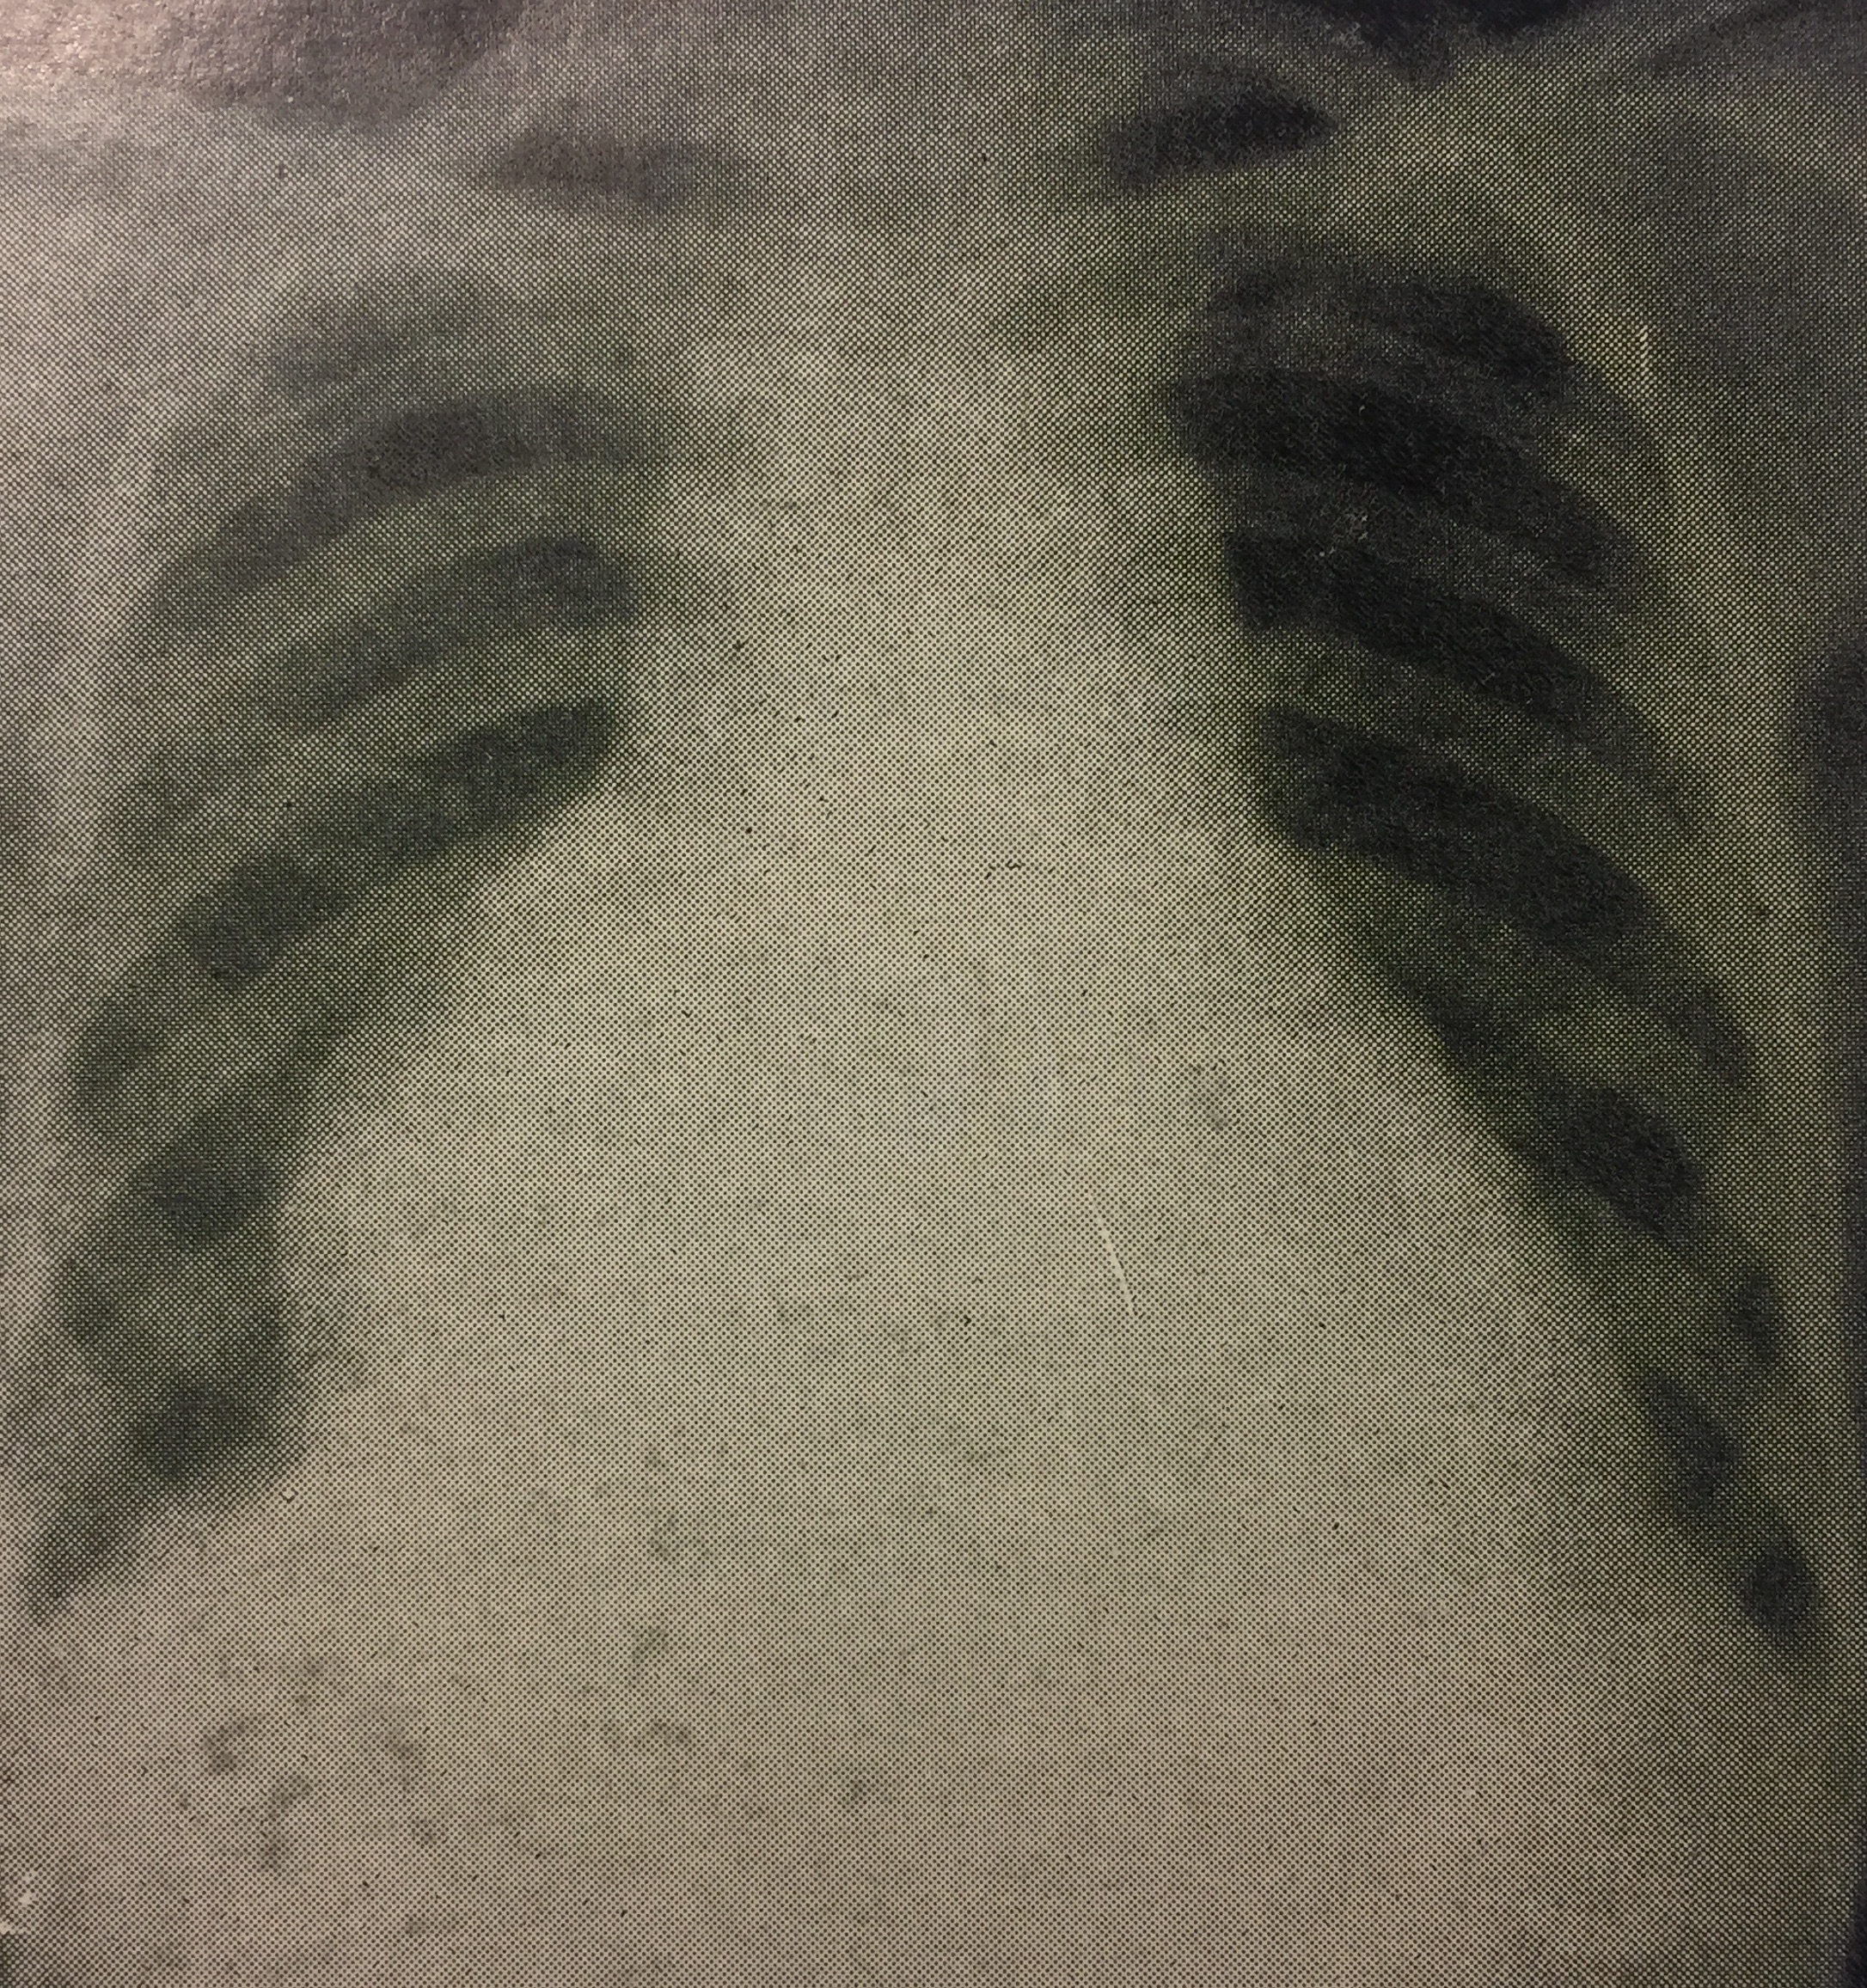

A breathless 20 year old with cough and fever

A 20 year old man complains of 3 weeks of cough and fever, and 4 days of oedema of his feet. On examination he is breathless. There is marked engorgement of his neck veins, JVP higher than ears, ascites, 2+ oedema of his feet. P130/min irregularly irregular, of waxing and waning volume, apex rate 160. BP 95/80. Liver 4cm. There was dullness and reduced breath sounds at R lung base. His chest radiograph is shown.

He has a pericardial effusion with tamponade. 500 mls of bloody fluid were drained from the pericardium, with immediate improvement in breathlessness and blood pressure. 1000 ml of similar fluid was drained from the right pleural cavity. Microscopy did not show a cause.